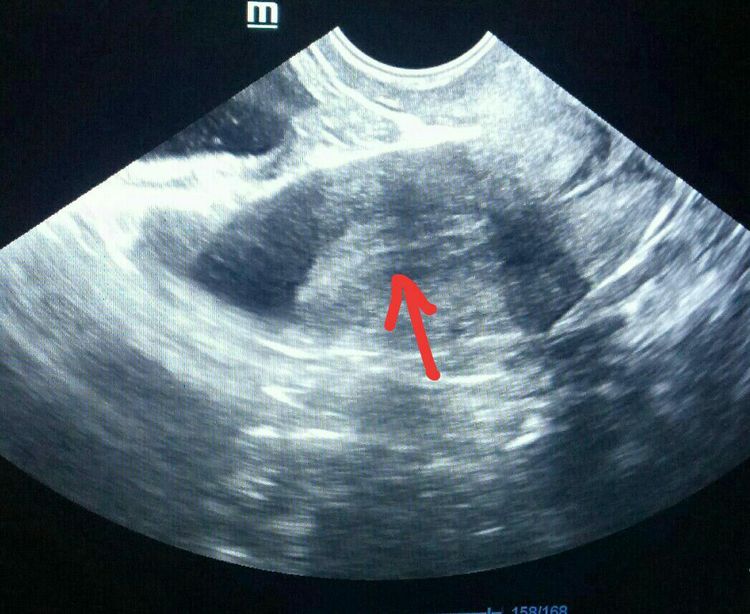

二、治疗输卵管积水,输卵管积水会返流回宫腔内,影响胚胎的着床,还会对子宫内膜造成损伤。治疗方法可以是结扎或者切除输卵管。